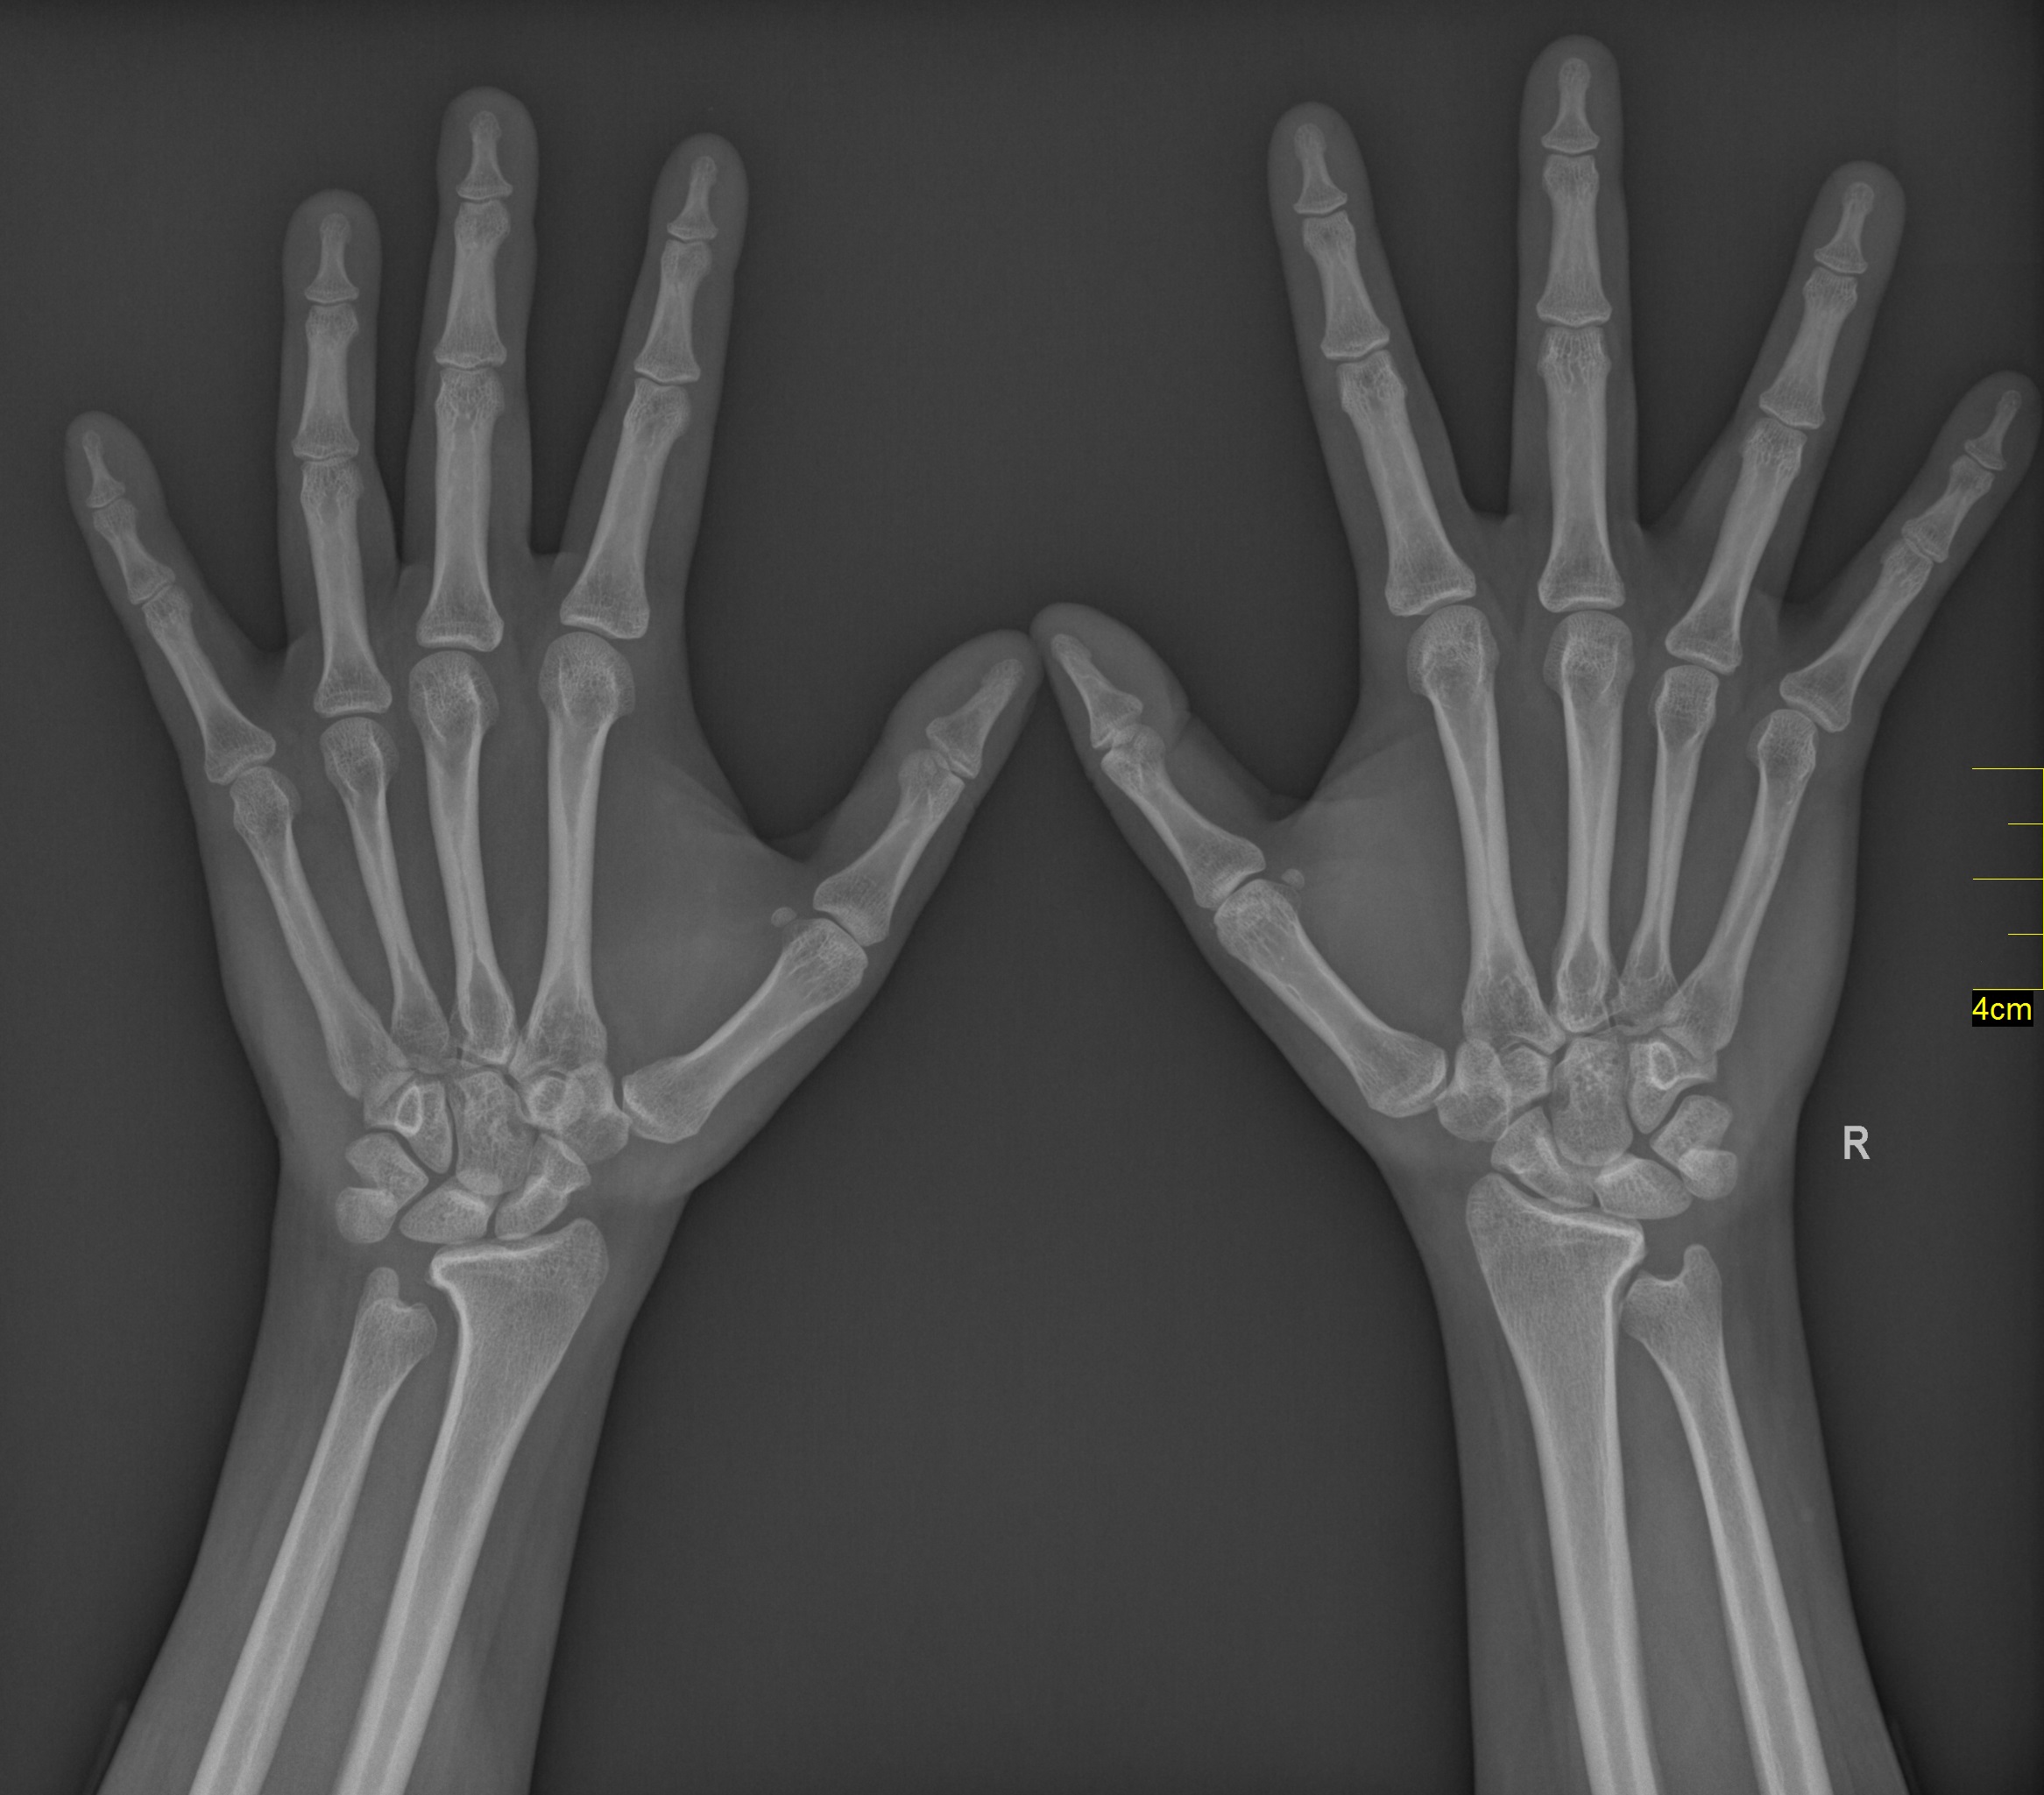

The seventh patient was a 30-year-old woman who presented with right wrist pain after a sports injury. There was no evidence of a fracture line on the radiographs. She had a full recovery after a 3-week protection. The radiographic follow-up evaluation indicated potential negative ulnar variance; a radiograph of both wrists was requested, which showed bilateral scalloping of the distal radius caused by a shortened ulna impinging on the distal radius proximal to the sigmoid notch. A bilateral metacarpal hypoplasia was additionally diagnosed on the radiographs involving the second to fourth metacarpals. She was referred with a diagnosis of bilateral ULD.

Physical and systemic examination, laboratory studies, and tests for autoimmune diseases at our service showed no abnormal findings. There was no radiographic evidence of similar changes in the metatarsals and no evidence of dwarfism or other syndromal disorders in the patient and her family. The radiographic appearance of obliteration of the central metacarpal intramedullary spaces was considered a variant. The final diagnosis was congenital bilateral negative ulnar variance associated with asymptomatic ulnar impingement syndrome (Figure 7).

Figure 7. A 30-year-old woman with bilateral negative ulnar variance associated with asymptomatic ulnar impingement syndrome. Diminished bilateral medullary cavity width is evident in the second to fourth metacarpals.